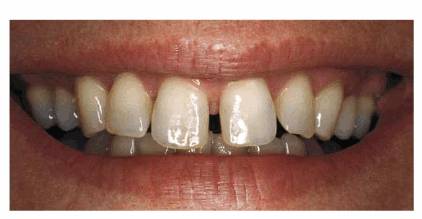

PROBLEM: This 43-year-old male presented with multiple diastemas between

the maxillary anterior teeth (see Figure 23-17A).

Figure 23-17A: This 43-year-old dentist was more concerned about the diastemas between his lateral incisors and cuspids than the space between the central incisors.

TREATMENT: Although porcelain laminates would be considered the

preferred treatment of choice today, the option of full crowns was chosen when

these teeth were restored. Therefore, six porcelain-fused-to-metal crowns were

constructed to close the anterior diastemas because the natural teeth were too

small for the space. Crowning with larger but proportionally sized teeth and

using principles of illusion (see Chapter 8, Figures 8-32A and B, Esthetics

in Dentistry, Volume 1, 2nd Edition) restored the man's appearance without

overly contouring any of the crowns. Because the patient had a somewhat rugged

look about him, anatomy was included in the restorations to give them

natural-looking shape and texture. Some wear was simulated on the incisors, and

a slight diastema was created between the central incisors to simulate the

arrangement of the original teeth. The patient had objected more to the large

spaces between the lateral incisors and cuspids than to the one between the

central incisors as when he smiled it looked as if he were missing his teeth.

The results can be seen in Figure 23-17B.

Figure 23-17B: Six aluminous porcelain crowns were placed to close the diastemas. However, the patient requested that a slight space be left between the central incisors to give him what he considered a more natural look.

RESULT: Sometimes,

it may take six crowns to close a diastema and create a symmetric result. There

are times when a patient will want to retain natural characteristics and even

duplicate a diastema on a smaller scale. If done well, this can effectively

reproduce the realism and naturalness of the original dentition. If this case

were to be restored using porcelain laminates, the esthetic principles

illustrated here would be the same.